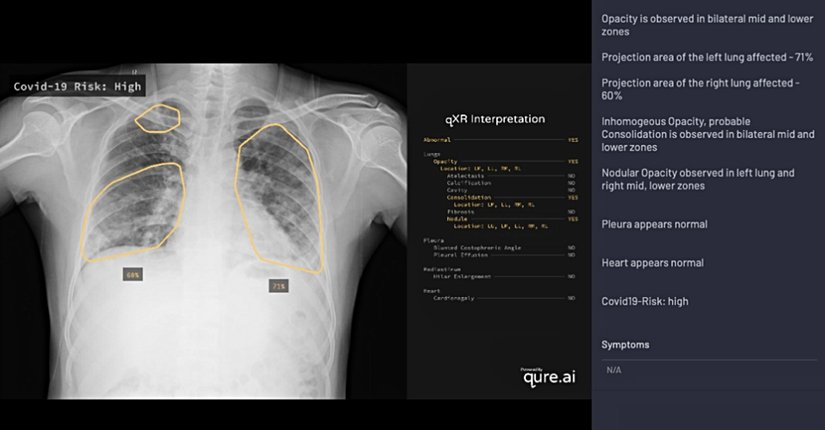

Qure.ai qXR sistemi sık görülen akciğer anomalilerini tespit etmek için derin öğrenme modelleri kullanmaktadır. COVID-19’a uyarlarken uzmanlara danışarak ve literatüre başvurarak COVID-19 pnömonisine ilişkin tipik özellikler değerlendirmeye alınmıştır. Bu bilgiler qXR’ye kodlanmış ve böylece bu enstrüman bu tarz bir görüntüyü taradığında covid-19 enfeksiyonu riskine ilişkin hesaplamalar yapacak duruma getirilmiştir. On bir görüntüyü kapsayan bir ön geçerlik çalışması COVID-19 hastalarının %95 hassasiyetle tespit edilebildiğini göstermiştir.